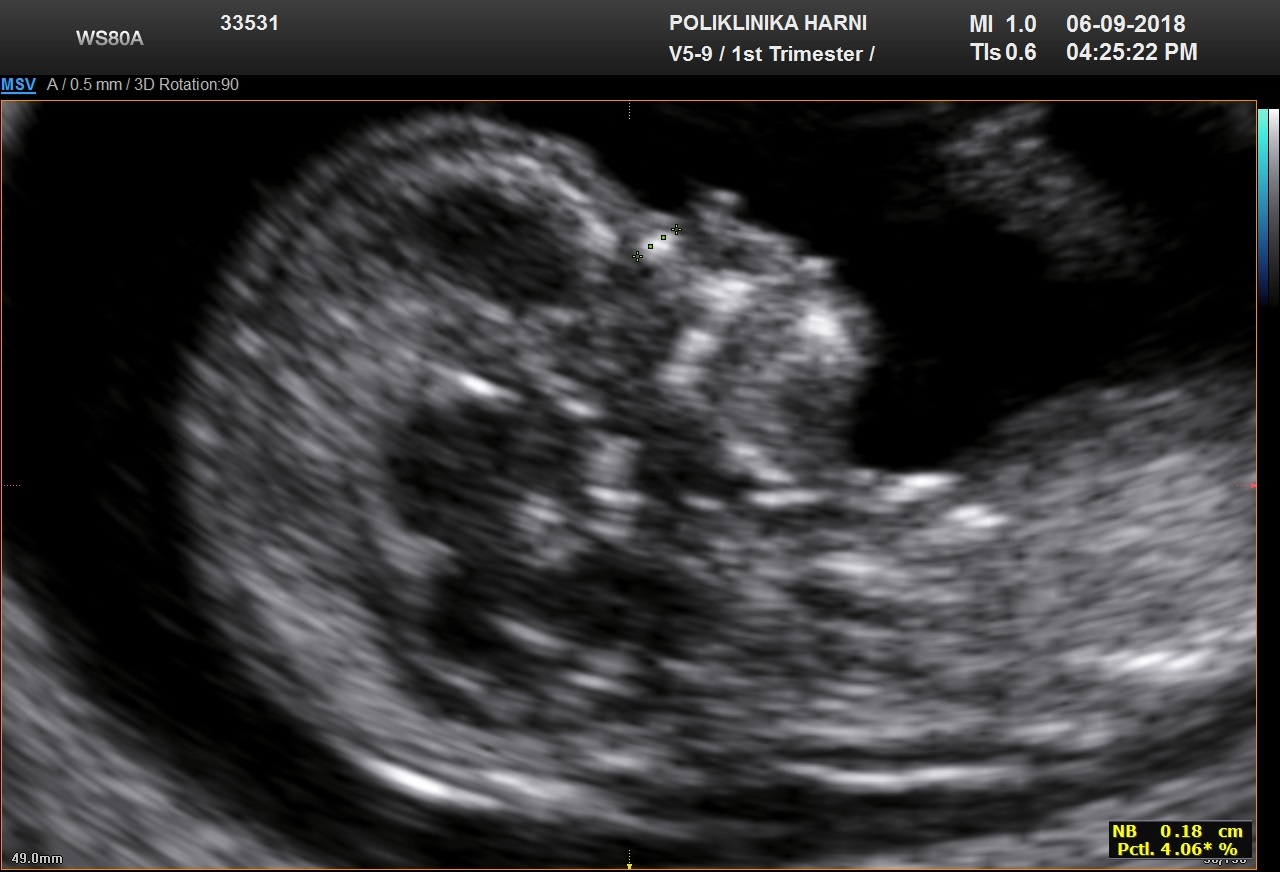

Nosna kost

Za procjenu nosne kosti fetusa, gestacija treba biti 11 + 0 do 13 + 6 tjedana, a CRL 45-84 mm.

Povećanje slike treba biti takvo da glava i gornji dio prsnog koš zauzimaju cijeli zaslon. Treba dobiti središnji sagitalni prikaz profila fetusa.

Ultrazvučna sonda mora biti paralelna smjeru nosa i lagano nagnuta s jedne na drugu stranu fetusa nosa.

Kad su ovi kriteriji zadovoljeni, treba prikazati tri različite linije na razini fetusa nosa:

- Gornja linija predstavlja kožu.

- Donja, koja je deblja i ehogenija od kože iznad nje, predstavlja nosnu kost.

- Treća linija ispred kosti i na višoj razini od kože predstavlja vrh nosa.

Smatra se da je nosna kost prisutna ako je ehogenija od kože i odsutna ako nije vidljiva ili je njezina ehogenost ista ili manja od one na koži.

Odsutna nosna kost

Sa 11-13 tjedana nosne kosti nema u:

- euploidnih fetusa 1-3%

- fetusa s trisomijom 21 60%

- fetusa s trisomijom 18 50%

- fetusa s trisomijom 13 40%